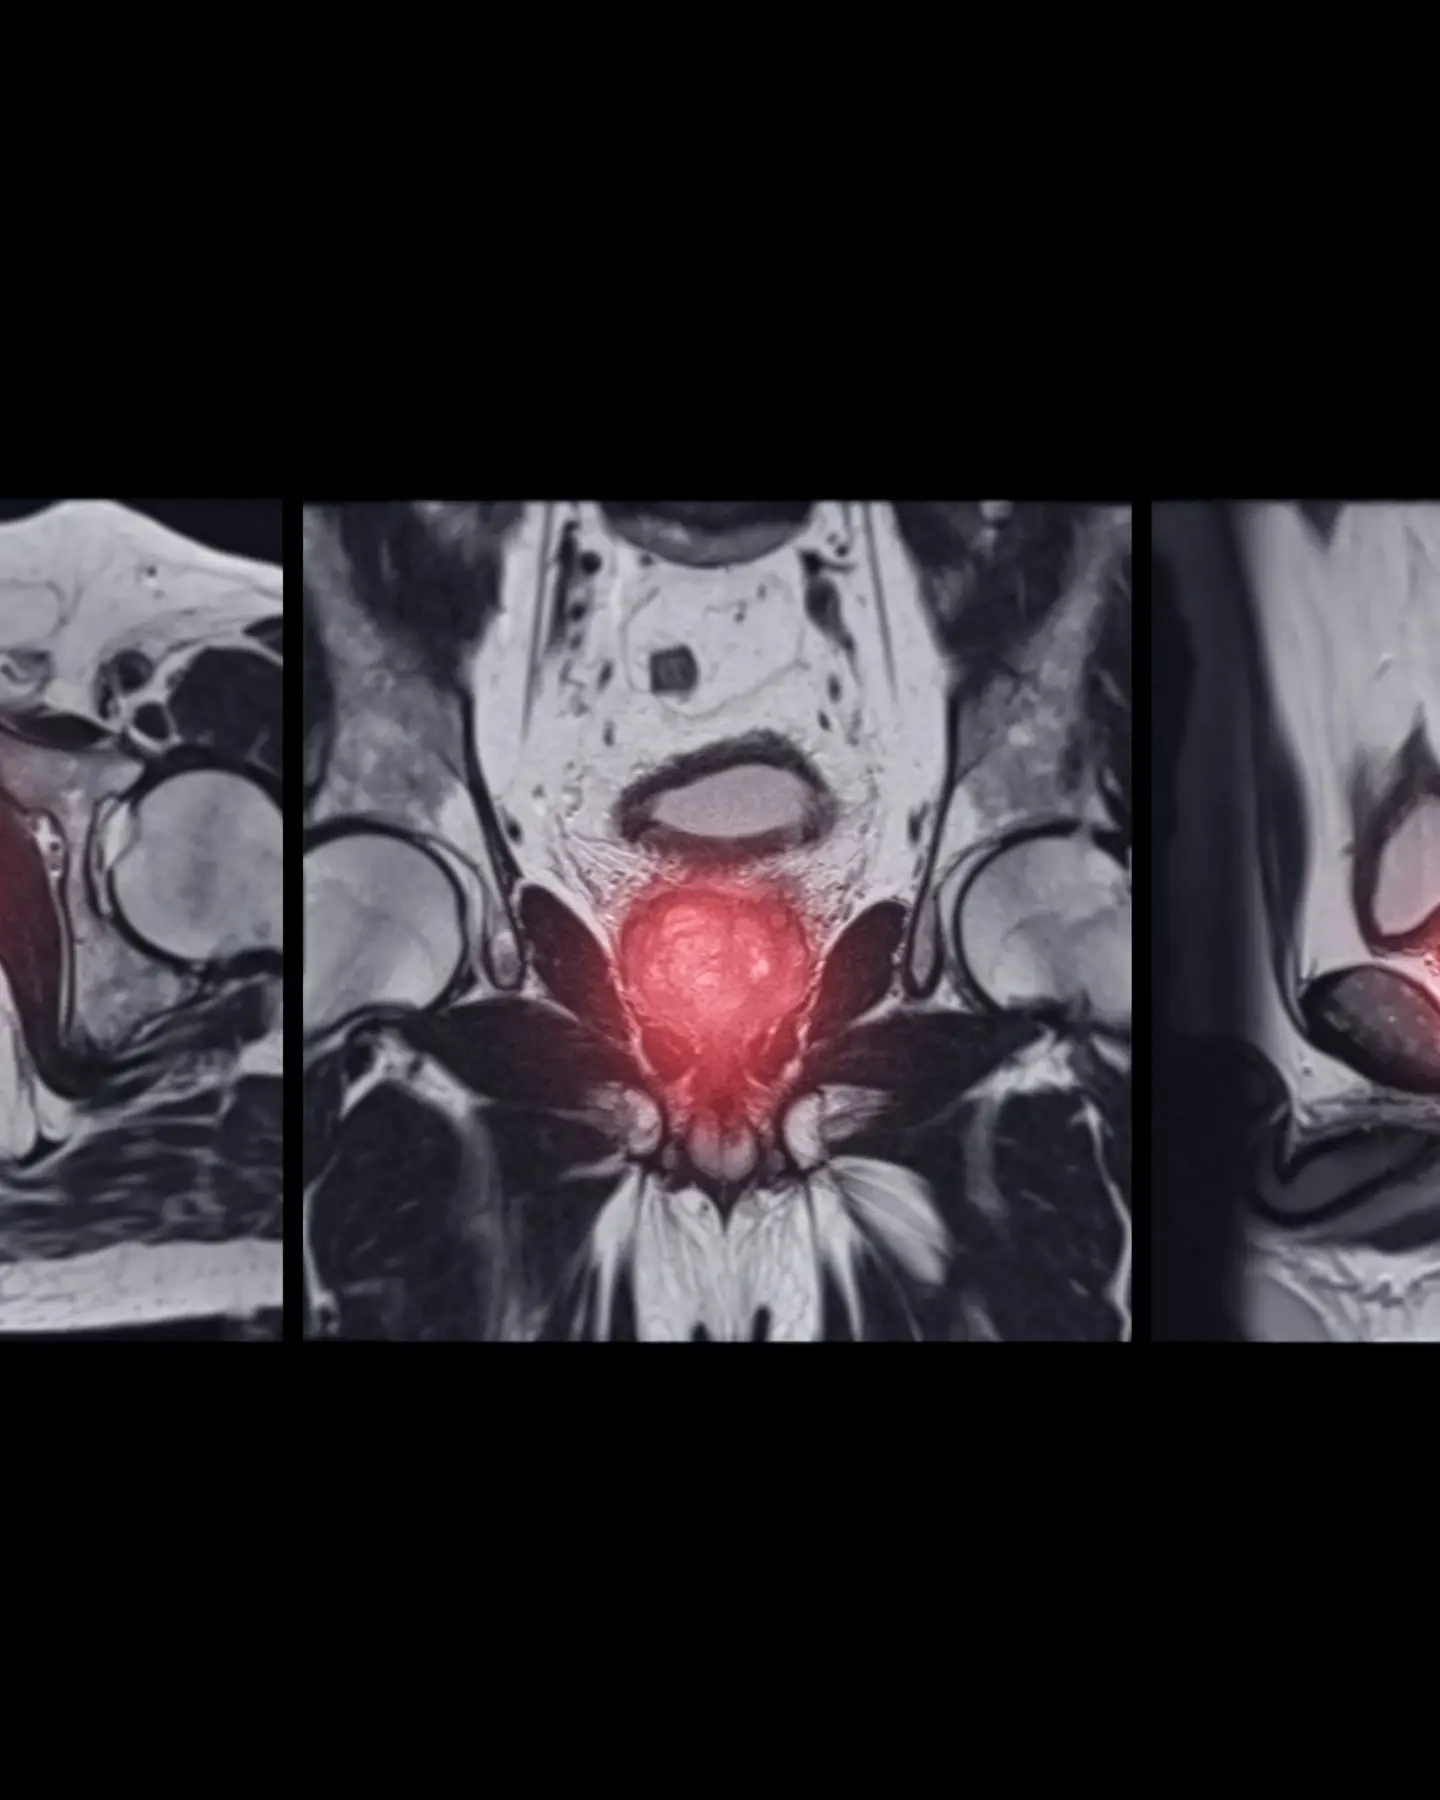

MRI Prostate Gland Axial Coronal And Agittal T2W

What conditions can a prostate MRI scan detect?

• Prostate Cancer

Prostate MRI is highly effective in identifying potential cancerous abnormalities within the prostate gland, enabling the recognition of suspicious regions that may need additional evaluation or biopsy.